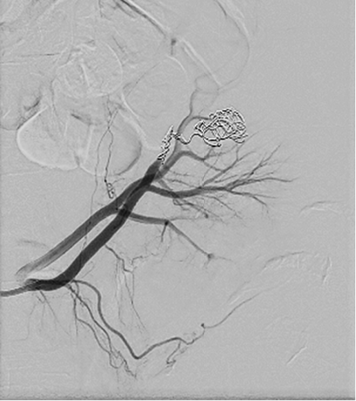

Cause of hematuria had to be determined, therefore urgent contrast enhanced computed tomography was performed (Figure 2) – contrast extravazation was found on the lower third of the right kidney (area of surgery), along with subcapsular hemathoma. Right hydroureteronephrosis and fluid in pelvis were observed. Blood clots and a small amount of contrast in the bladder were seen.

Figure 2. Contrast extravazation was found on the lower third of the right kidney (white arrow), subcapsular hemathoma (grey arrow)